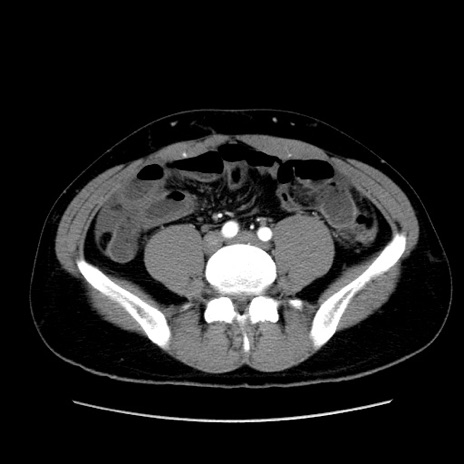

症例36(横断像)

【症例】20歳代 男性

【主訴】心窩部痛

【現病歴】今朝より上腹部痛あり。一旦軽快していたが再度出現したため救急要請。昨日夕に白身の魚を含む刺身を食べた。

【身体所見】BP 136/89mmHg、HR 74/min、BT 37.0℃、腹部:膨満、軟、心窩部に圧痛あり。反跳痛なし、筋性防御なし、腸雑音やや亢進あり。

【データ】WBC 17700、CRP 0.48